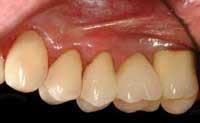

This amount of treatment may be more than the patient can afford in one year, even when using any third–party benefit that is present. If so, segment the first portion into more piecemeal treatment, doing only the mandatory therapy first. As an example, if a significant amount of therapy has been needed before treating the six anterior teeth, these teeth may be treated in the second year. However, I prefer treating the upper anterior teeth in the first year if possible. Often, the anterior teeth can be treated conservatively rather than using crowns, to provide even more motivation for the patient to continue with the therapy. (See Fig. 4.)

Year two: Select the most debilitated quadrant of posterior teeth, and do whatever needs to be done in that quadrant. This treatment will probably amount to anything up to four crowns, or some implants and implant–supported prostheses. (See Fig. 5.)